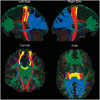

Primary lateral sclerosis is a sporadic disorder characterized by slowly progressive corticospinal dysfunction. Primary lateral sclerosis differs from amyotrophic lateral sclerosis by its lack of lower motor neuron signs and long survival. Few pathological studies have been carried out on patients with primary lateral sclerosis, and the relationship between primary lateral sclerosis and amyotrophic lateral sclerosis remains uncertain. To detect in vivo structural differences between the two disorders, diffusion tensor imaging of white matter tracts was carried out in 19 patients with primary lateral sclerosis, 18 patients with amyotrophic lateral sclerosis and 19 age-matched controls. Fibre tracking was used to reconstruct the intracranial portion of the corticospinal tract and three regions of the corpus callosum: the genu, splenium and callosal fibres connecting the motor cortices. Both patient groups had reduced fractional anisotropy, a measure associated with axonal organization, and increased mean diffusivity of the reconstructed corticospinal and callosal motor fibres compared with controls, without changes in the genu or splenium. Voxelwise comparison of the whole brain white matter using tract-based spatial statistics confirmed the differences between patients and controls in the diffusion properties of the corticospinal tracts and motor fibres of the callosum. This analysis further revealed differences in the regional distribution of white matter alterations between the patient groups. In patients with amyotrophic lateral sclerosis, the greatest reduction in fractional anisotropy occurred in the distal portions of the intracranial corticospinal tract, consistent with a distal axonal degeneration. In patients with primary lateral sclerosis, the greatest loss of fractional anisotropy and mean diffusivity occurred in the subcortical white matter underlying the motor cortex, with reduced volume, suggesting tissue loss. Clinical measures of upper motor neuron dysfunction correlated with reductions in fractional anisotropy in the corticospinal tract in patients with amyotrophic lateral sclerosis and increased mean diffusivity and volume loss of the corticospinal tract in patients with primary lateral sclerosis. Changes in the diffusion properties of the motor fibres of the corpus callosum were strongly correlated with changes in corticospinal fibres in patients, but not in controls. These findings indicate that degeneration is not selective for corticospinal neurons, but affects callosal neurons within the motor cortex in motor neuron disorders.